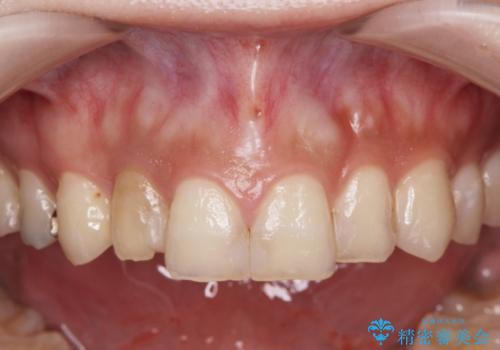

レジン修復による充填は、劣化し、色調の変化による審美障害が生じることが多々あります。

ある程度の大きさになった充填物は、劣化の少ないセラミッククラウンにすることで色調の劣化を抑え、審美性を保つことができます。